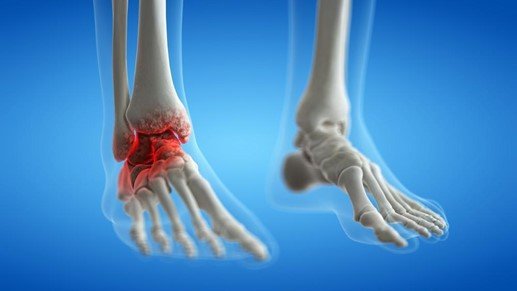

Ankles affected with rheumatoid arthritis

- An autoimmune condition where the body attacks the synovial lining of the joint, leading to chronic inflammation.

- Over time, this can damage cartilage, ligaments, and bones, resulting in joint deformity and instability.

- Symptoms include prolonged morning stiffness, swelling, warmth, and redness around the joint.

- If untreated, rheumatoid arthritis can lead to severe disability and deformity in the ankle joint.